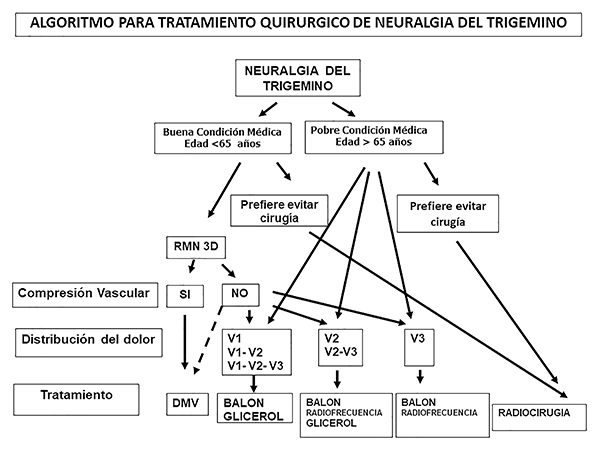

Figura 1: Algoritmo de tratamiento quirúrgico para la neuralgia del trigémino.

Utilizamos un algoritmo de tratamiento quirúrgico para los pacientes con neuralgia del trigémino (Figura 1). Se explicaron las ventajas y riesgos de las diferentes opciones de tratamiento quirúrgico y finalmente el paciente decidió según su preferencia.

Figura 1: Algoritmo de tratamiento quirúrgico para la neuralgia del trigémino.